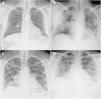

A y B) Varón de 49 años, exfumador desde hace 5 años, con antecedentes de hipertensión arterial, dislipemia, cardiopatía hipertensiva, hiperuricemia, trasplante renal y tiroidectomía total por carcinoma papilar de tiroides. Acude por fiebre, tos seca y mialgias de 4 días de evolución. Datos de laboratorio: leucocitos 7.100/μL, linfocitos 600/μL (linfocitos/leucocitos 7,7%), plaquetas 140.000/μL, PCR 1,63mg/dL, dímero D 754 ng/mL y LDH 471 U/L. Radiografía de tórax posteroanterior del 16 de marzo de 2020 donde se observa una opacidad en vidrio deslustrado, periférica, en el campo medio derecho (score=1) (flecha). El paciente ingresó y en la radiografía de tórax del día 24 de marzo de 2020 se ve un claro empeoramiento radiológico con consolidaciones pulmonares bilaterales, más extensas (flechas), asociado a un incremento de las necesidades de oxigenoterapia. C y D) Mujer de 33 años, procedente de Guatemala, sin antecedentes personales de interés, que acude al servicio de urgencias derivada por su médico de atención primaria por tos y fiebre de 9 días de evolución. Analítica sanguínea: leucocitos 5.100/μL, linfocitos 1.400/μL (linfocitos/leucocitos 27,9%), plaquetas 224.000/μL, PCR 8,44mg/dL, dímero D 500 ng/mL y LDH 666 U/L. En la radiografía de tórax posteroanterior del 17 de marzo de 2020 se identifican consolidaciones pulmonares bilaterales, parcheadas y de predominio en los lóbulos inferiores (score=5) (flechas). La paciente ingresó y 2 días después presentó empeoramiento clínico y analítico, observándose en la radiografía del día 23 de marzo un empeoramiento radiológico, con confluencia de las consolidaciones previas.